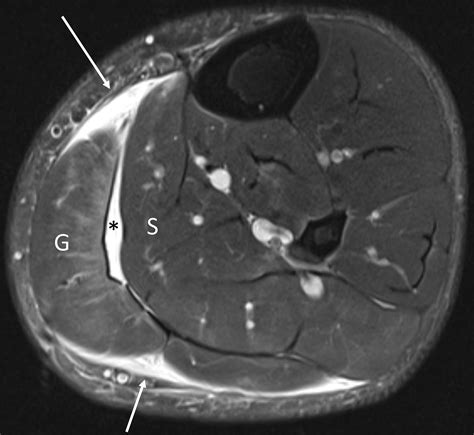

• Order imaging tests such as an ultrasound or MRI to confirm the diagnosis and determine the severity of the tear.

• gastrocnemius muscle tear mri